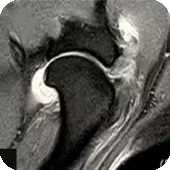

Nowoczesny aparat Esaote zaadaptowany do badań w weterynarii (neurologia, ortopedia, diagnostyka guzów).

Obrazowanie 2D i 3D (RM trójwymiarowe) dla precyzyjnej analizy zmian chorobowych.

Badania z podaniem kontrastu, zwiększające szczegółowość obrazowania.

Obraz RM mózgu psa